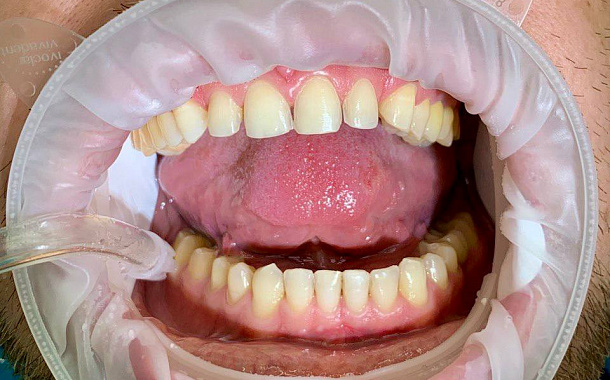

- Точное планирование: Детальные 3D-модели позволяют нашим специалистам тщательно спланировать каждый этап лечения, учитывая все анатомические особенности пациента.

- Визуализация результатов: Пациенты могут увидеть предполагаемый результат лечения еще до его начала, что помогает в принятии информированных решений.

- Минимизация погрешностей: Высокая точность сканирования снижает риск ошибок при изготовлении протезов и реставраций.